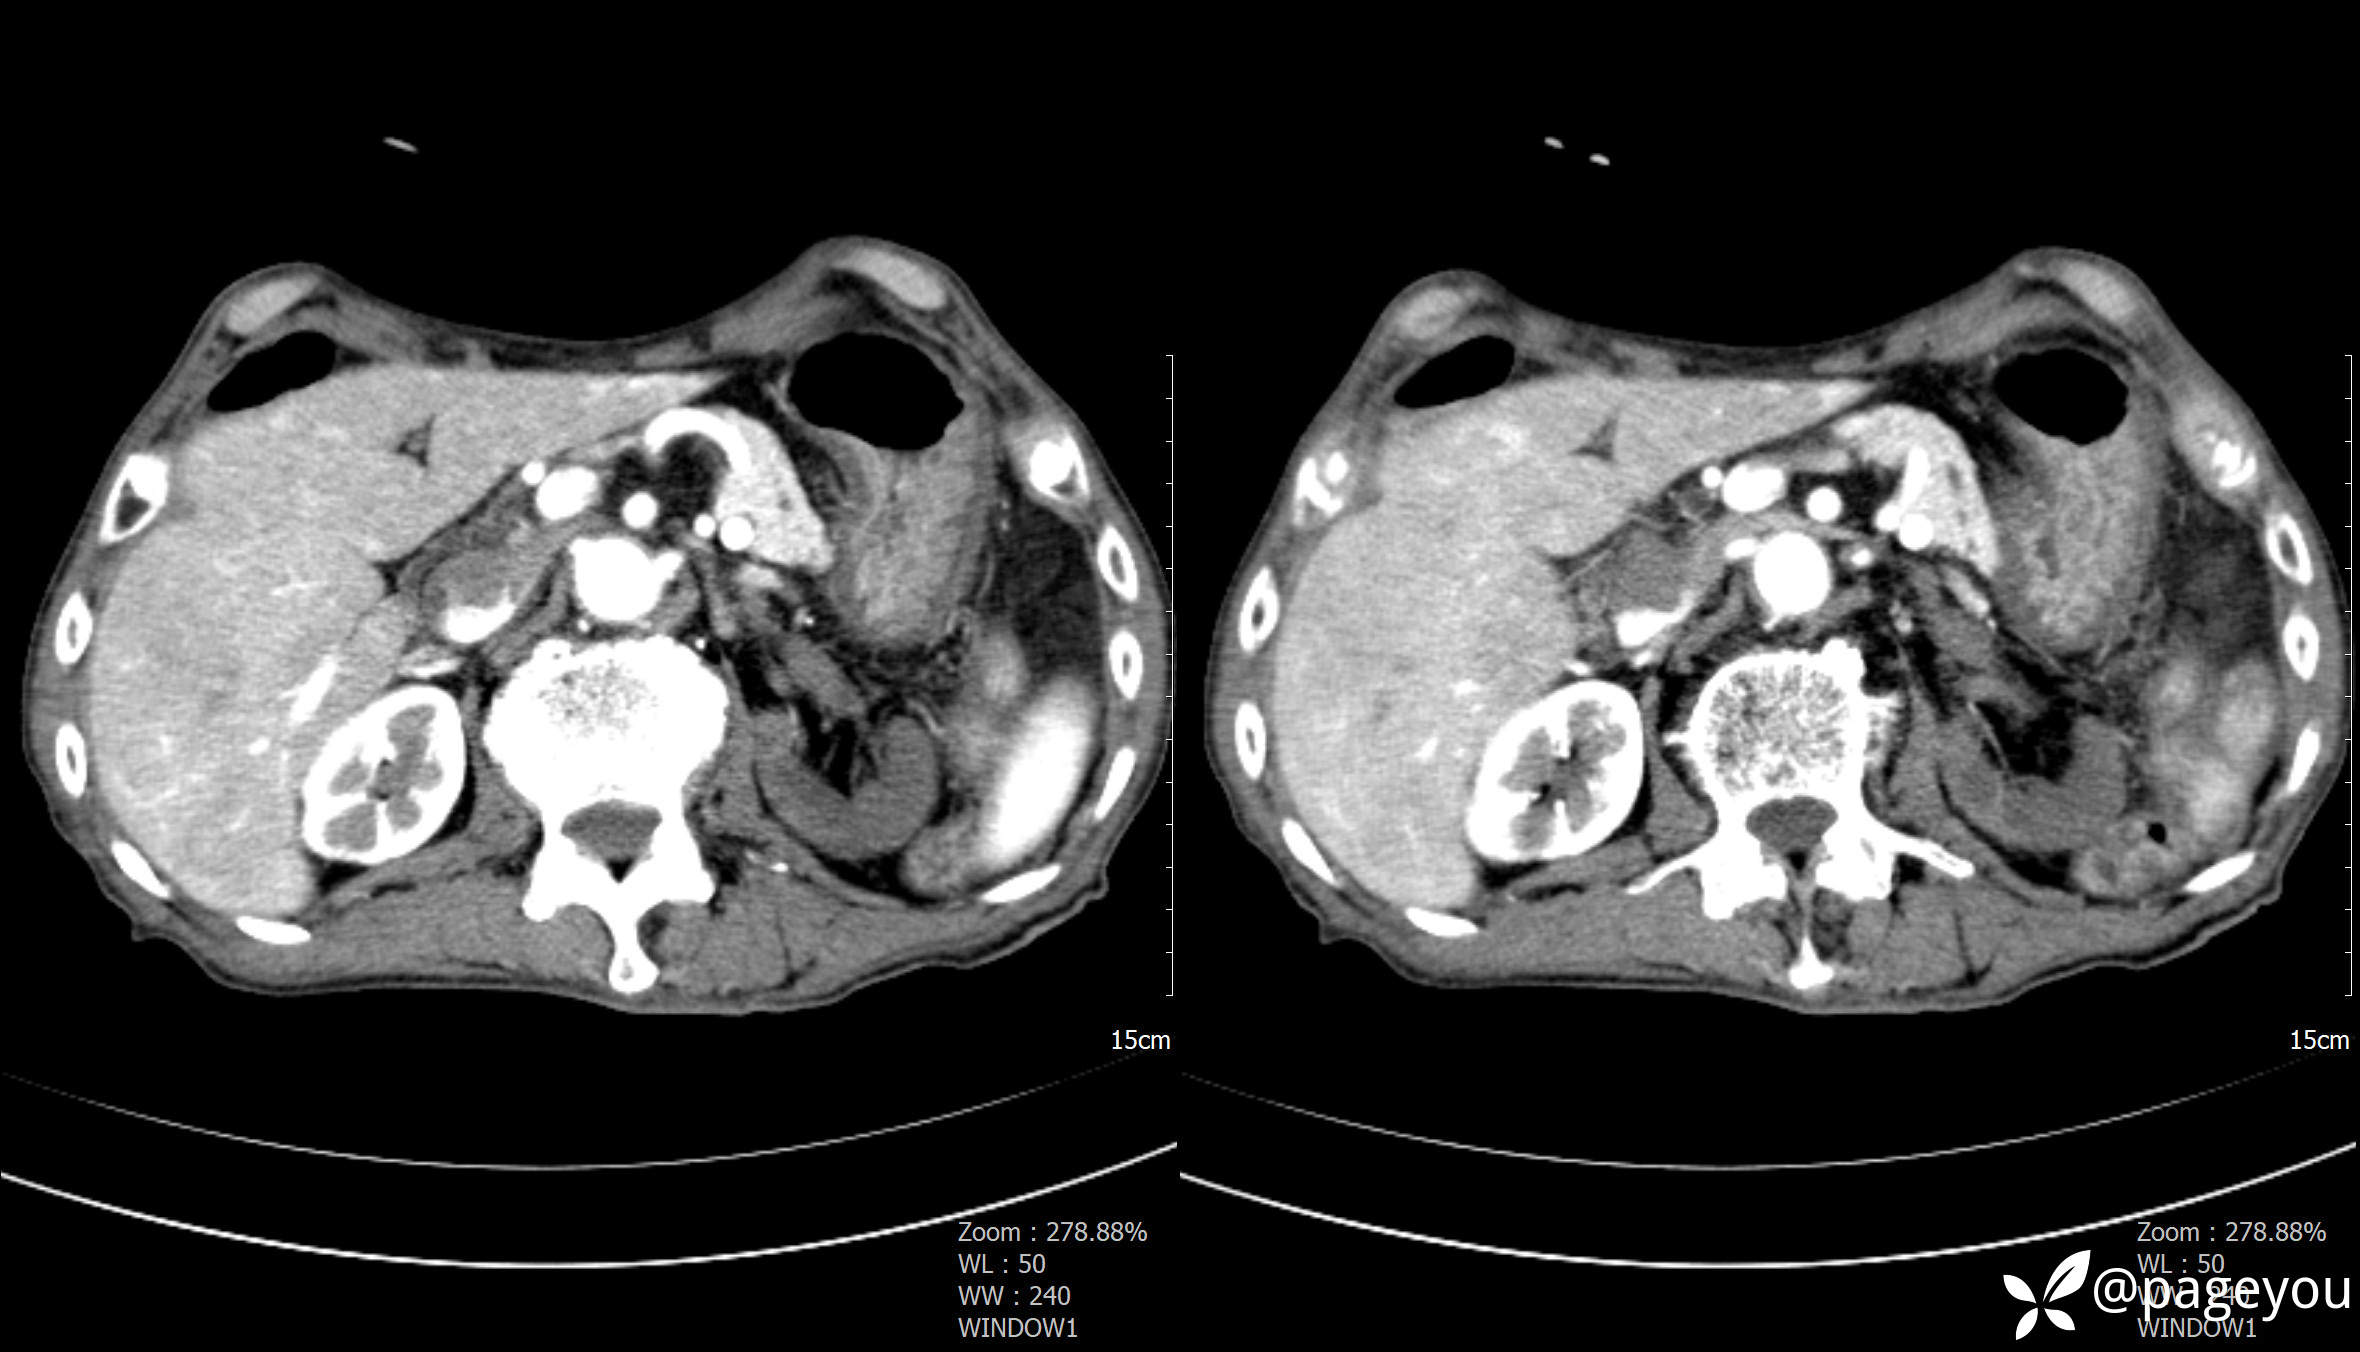

主动脉CTA: